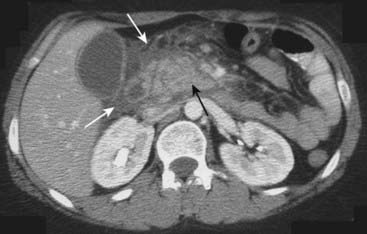

Figure 18-24 Pancreatic pseudocyst.

Pseudocysts (P) of the pancreas occur when fibrous tissue encapsulates a walled-off collection of pancreatic juices released from the inflamed pancreas. Pseudocysts may have an enhancing wall (solid white arrow). The cyst is indenting a loop of adjacent bowel, in this case the posterior wall of the stomach (S). The indentation on a loop of bowel by an extrinsic mass is called a pad sign (solid black arrow).